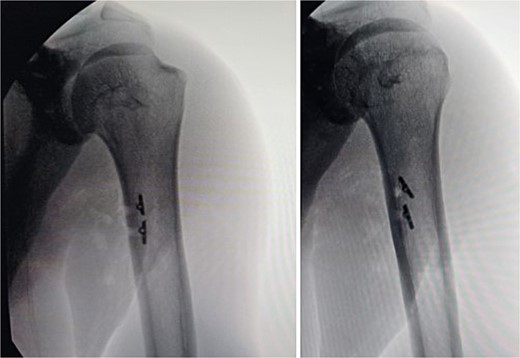

Given the complete rupture on the MRI and the high functional demand of the patient, surgical treatment was indicated and performed 10 days post-injury. The patient was positioned in a right lateral decubitus position with the left upper limb in 90° abduction (Fig. 3). A single 8 cm incision was made at the posterior axillary fold (Fig. 4). After identifying the radial nerve, a complete tear of the teres major at the myotendinous junction was visualized (Fig. 5). The tendon was tied with FiberWire (Arthrex, Naples, FL, USA) (Fig. 6) and its mobility confirmed. The humeral insertion site was exposed, debrided, drilled with two parallel holes 3 cm apart, and fixed with two Pec Buttons. The sutures were tensioned to stabilize the tendons. The shoulder’s range of motion was evaluated, confirming adequate repair tension (Fig. 7), and the incision was sutured. Final intra-op radiographic image is shown in Fig. 8. Post-surgery, no neurovascular changes were noted.

Post-surgery anteroposterior radiographies of the arm showing both Pec Buttons used for the teres major repair.